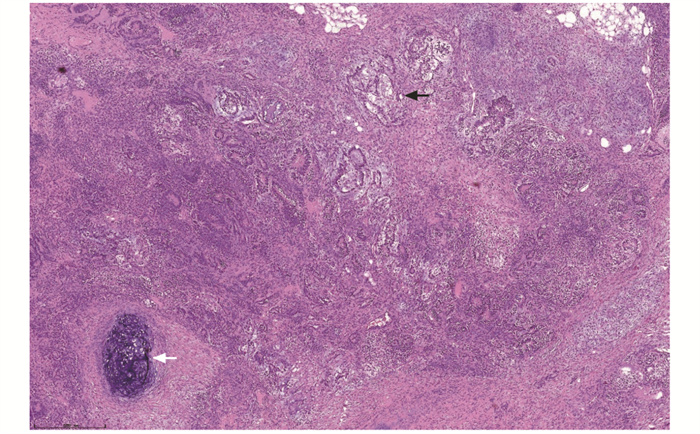

结果  共纳入睾丸和附件病变患者317例,平均年龄(38.72±19.74)岁,临床症状以阴囊区肿大、疼痛为主(88.01%, 279/317),肿瘤性疾病85例(26.81%,85/317)、非肿瘤性疾病232例(73.19%,232/317)。病变组织大体表现:肿瘤性疾病的病灶直径2~17 cm,呈结节或分叶状,切面为实性或囊实性,部分区域可见出血或坏死;非肿瘤性疾病的病灶直径0.6~8 cm,多呈囊性,囊壁较光滑,部分呈实性结节状。85例肿瘤性疾病患者中,平均年龄(38.09±14.52)岁,恶性肿瘤占比96.47%,肿瘤类型依次为生殖细胞肿瘤(88.24%,75/85)、淋巴造血系统肿瘤(4.71%,4/85)、间叶肿瘤(4.71%, 4/85)、间质细胞瘤(1.18%,1/85)、附睾乳头状囊腺瘤(1.18%,1/85),其中生殖细胞肿瘤中,主要为精原细胞瘤(66.67%,50/75),其次为混合性生殖细胞肿瘤(14.67%,11/75)、胚胎性癌(12.00%,9/75)。4例淋巴造血系统肿瘤均为弥漫性大B细胞淋巴瘤。232例非肿瘤性疾病患者中,平均年龄(38.94±21.36)岁,以鞘膜积液最为常见(56.03%,130/232),其次为炎症性疾病(31.03%,72/232)、睾丸发育异常(8.62%,20/232),睾丸扭转/梗死(3.88%,9/232)和睾丸附件囊肿(0.43%,1/232)较少见。睾丸与附睾结核(77.78%,56/72)是炎症性疾病的最主要类型。

Results  There were 317 cases of testicular and adnexal lesions diagnosed by pathology, with the mean age of (38.72±19.74) years and the clinical manifestations mainly characterized by swelling and pain in the scrotum area (88.01%, 279/317). There were 85 cases of neoplastic diseases (26.81%, 85/317), in which malignant tumors accounted for 96.47%, with an average age of (38.09±14.52) years. There were 232 cases of non-neoplastic diseases (73.19%, 232/317), with an average age of (38.94±21.36) years. The gross manifestations of the lesions were as follows: the lesions of the neoplastic disease were 2-17 cm in diameter and were nodular or lobulated, the sections were solid or cystic-solid, and bleeding or necrosis could be seen in some areas; the lesions of non-neoplastic diseases were 0.6-8 cm in diameter and were mostly cystic with smooth cystic wall, and some lesions were solid nodules. Among neoplastic diseases, the tumor types were germ cell tumors (88.24%, 75/85), lymphohematopoietic tumors (4.71%, 4/85), mesenchymal tumors (4.71%, 4/85), leyding cell tumor(1.18%, 1/85), and papillary cystadenoma of the epididymis (1.18%, 1/85). Among germ cell tumors, seminoma were mainly type (66.67%, 50/75), followed by mixed germ cell tumor (14.67%, 11/75), embryonal carcinoma (12.00%, 9/75). All 4 cases of lymphohematopoietic tumor were diffuse large B-cell lymphoma. Among non-neoplastic diseases, hydrocele accounted for 56.03% (130/232), followed by inflammatory diseases (31.03%, 72/232) and testicular dysplasia (8.62%, 20/232), testicular torsion/infarction (3.88%, 9/232) and testicular adnexal cyst (0.43%, 1/232) accounted for a lower proportion. Testicular and epididymal tuberculosis (77.78%, 56/72) was the main type of inflammatory diseases.